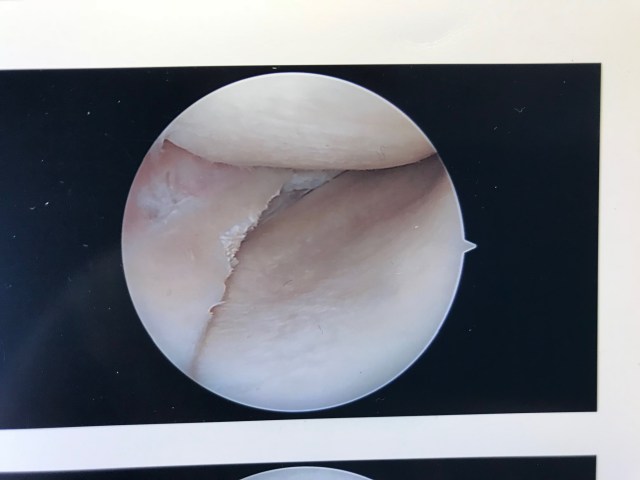

I’m not about make any money or get many likes on my Instagram for the naughty-looking pictures of the inside of my knee. Because when you look at the photo below and see the hole where my ACL used to be, the dark void tells a sad story.

Finally the knee did start to hurt. Which led to the visit to the doctor, and the MRI that showed a chunk of meniscus torn inside my knee. That led to surgery and these before and after photos of the excision being performed on a torn meniscus. What a delightful little montage of knee porn.

I find my knee porn images somewhat funny. If these were dick pics or a closeup of some woman’s vagina, this blog would be Rated R and the content considered scandalous. The second image does look quite a bit like a shaved mons venus. But since these images were actually taken inside my knee, they have no scandal value at all. In fact, they mean very little to anyone but me.